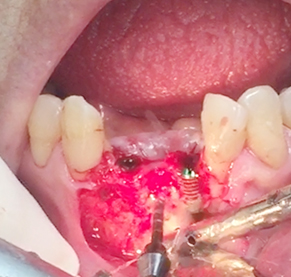

Implants/Bone Grafting

Simultaneous bone graft and implant placement